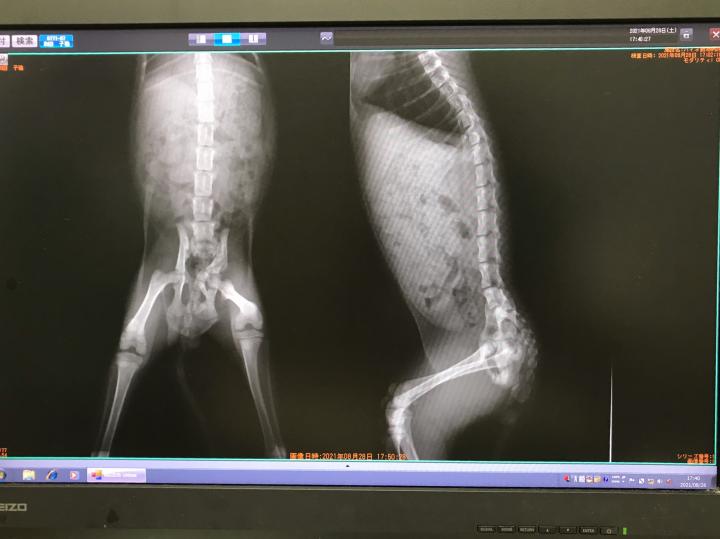

ちなみにレントゲンも撮ってきました!

やはりこれ以上折れていた部分が広がる事はなさそうです

しかし上手い具合に左右で少し出っ張り部分がズレているので排便には問題がないのかもしれないと仰って頂きました!

まだ成長課程の身体ですので完治ではありませんが

次のレントゲンは2〜3ヶ月先で大丈夫との事!

このままいけば骨盤拡張手術はやらなくても大丈夫そうな説明でしたので少し安心しましたε-(´∀`*)ホッ